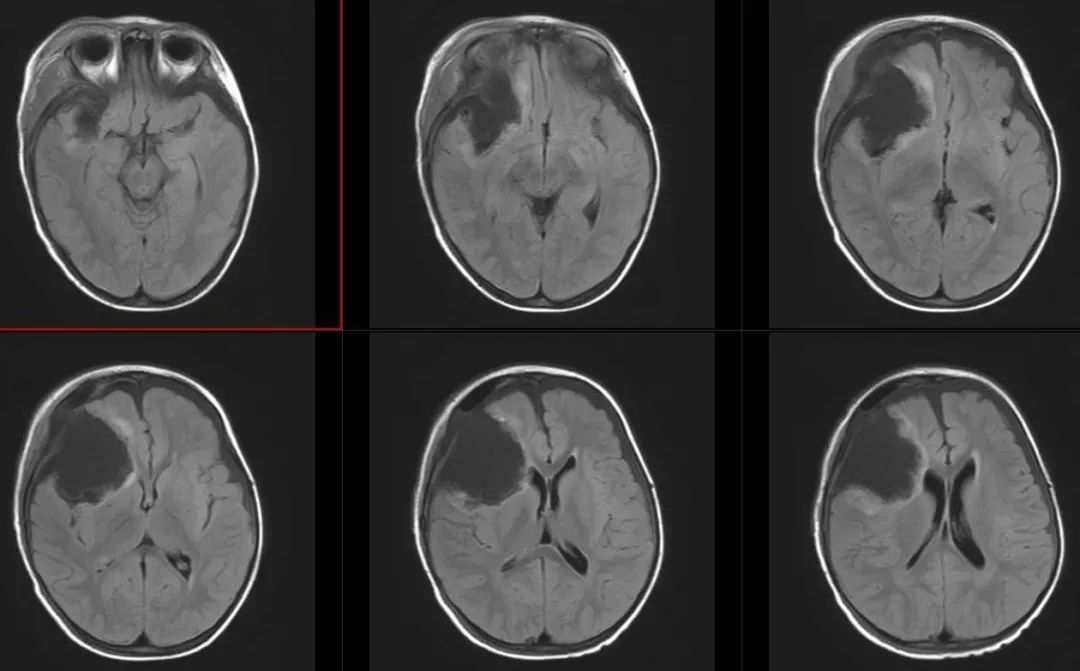

术前影像

术前T1轴位